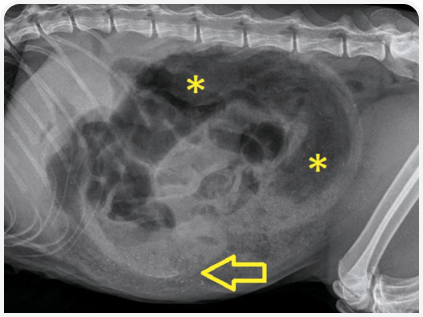

Пальпация брюшной полости без признаков отклонений не позволяет полностью исключить заболевания; даже при легкой форме заболевания проводят рентгенографию органов брюшной полости и в случае необходимости — хирургическое лечение. Если при рентгенографии не выявляют инородное тело (например, оно нерентгеноконтрастное), нужно оценить его непрямые симптомы, такие как центральное «скопление» петель кишечника (Рисунок 1) или аномальные пузырьки кишечного газа в форме полумесяца или слезы (5). Наличие так называемого симптома гравийных камешков указывает на хроническую кишечную непроходимость (Рисунок 2).

Инородные тела в кишечнике, помимо линейных, обычно вызывают его полную непроходимость с расширением краниально расположенных петель тонкой кишки (5). Аналогичным образом, в некоторых случаях хронических заболеваний ЖКТ (особенно у молодых кошек) может наблюдаться хроническая/динамическая инвагинация кишечника без явного расширения кишечных петель. Очень важно получить две, а лучше три рентгенограммы органов брюшной полости (лево- и правосторонние боковые и в ортогональной проекции), поскольку важнейшие нарушения могут выявляться только на одном снимке (Рисунок 3).